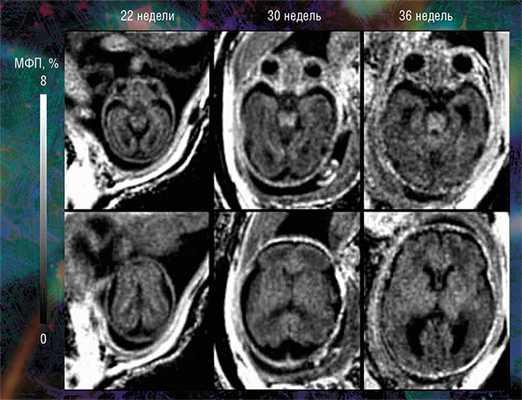

Пилотные исследования, выполненные в рамках клинических диагностических МРТ-обследований эмбрионов возрастом от 20 недель и старше, показали, что новая технология позволяет за небольшое (менее 5 мин.) время сканирования выявить очень малые количества миелина.

Они также подтвердили способность метода надежно оценивать пространственно-временные «траектории развития» миелина в различных структурах мозга. Судя по результатам исследования, в центральных структурах (стволовых, таламусе, мозжечке) процесс миелинизации начинается раньше, а ее степень пропорциональна возрасту. При этом в белом веществе полушарий головного мозга миелин в дородовом периоде практически не обнаруживается (Yarnykh, Prihod’ko, Savelov et al., 2018). Полученные новым неивазивным методом результаты хорошо согласуются с уже известными патоморфологическими данными.

С его помощью новосибирским специалистам впервые удалось разработать количественные критерии нормальной внутриутробной миелинизации, на основании которых можно оценить своевременность формирования внутренней структуры мозга от второго триместра до рождения ребенка. Эти критерии в дальнейшем можно использовать в клинической практике. Кроме того, в некоторых случаях новый метод помогает диагностировать врожденный порок развития головного мозга еще до рождения, что бывает затруднительно с использованием только традиционных методов МРТ.